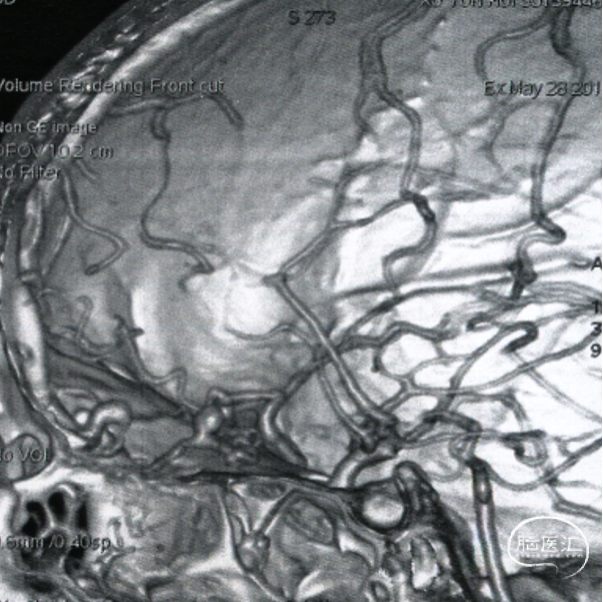

CTA提示前颅窝底异常扩张的血管。

双侧颈内动脉正侧位造影见前颅窝底硬脑膜动静脉瘘,双侧筛前动脉、筛后动脉向瘘口供血,通过皮层静脉向上矢状窦引流。

双侧颈外动脉正侧位造影见镰前动脉向瘘口供血。

左侧椎动脉正侧位造影未见明显异常。